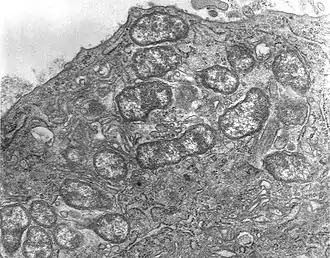

| Фотография микропрепарата Orientia tsutsugamushi | |